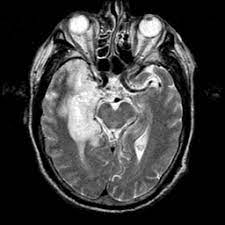

The basal ganglia are usually spared. Mri is the diagnostic modality of choice abnormal in 90%; Hsv encephalitis | radiology case | radiopaedia.org. Axial t2 prominent swelling, increase t2 signal involving the left temporal lobe and insular cortex. For a general discussion, and for links to other system specific manifestations, please refer to the article on hydatid disease. Herpes simplex (hsv) encephalitis is the most common cause of fatal sporadic fulminant necrotizing viral encephalitis and has characteristic imaging findings. Herpes simplex virus (hsv) is a human herpesvirus that causes hsv encephalitis (hse), which is the commonest fatal sporadic encephalitis in humans. Hse may result from primary infection or reactivation from latency, and it frequently involves frontal or temporal lobes, as well as the brain stem. The differential diagnoses include limbic encephalitis (paraneoplastic), gliomatosis cerebri, and status epilepticus. A brain biopsy was performed and the histology was consistent with encephalitis. For a general discussion, and for links to other system specific manifestations, please refer to the article on hydatid disease. Cerebral malaria is a rare intracranial complication of a malarial infection. Bilateral temporal lobe t2 hyperintensity refers to hyperintense signal involving the temporal lobes on t2 weighted and flair imaging.

For a general discussion, and for links to other system specific manifestations, please refer to the article on coccidioidomycosis. But changes are not specific for hsv (e.g. Multilocularis, and describes a spectrum of disease involving the spinal cord, the spine, or both. There is also some cortical ribboning seen on dwi. Cerebritis is a term that represents inflammation of the brain in the setting of infection, before the development of a cerebral abscess. Cerebral malaria is a rare intracranial complication of a malarial infection. Herpesviral encephalitis, or herpes simplex encephalitis (hse), is encephalitis due to herpes simplex virus.it is estimated to affect at least 1 in 500,000 individuals per year, and some studies suggest an incidence rate of 5.9 cases per 100,000 live births. Herpes simplex (hsv) encephalitis is the most common cause of fatal sporadic fulminant necrotising viral encephalitis and has characteristic imaging findings.

The differential diagnoses include limbic encephalitis (paraneoplastic), gliomatosis cerebri, and status epilepticus. Ventriculitides) refers to inflammation, usually due to infection, of the ependymal lining of the cerebral ventricles. For a general discussion, and for links to other system specific manifestations, please refer to the article on coccidioidomycosis. Herpes simplex (hsv) encephalitis is the most common cause of fatal sporadic fulminant necrotising viral encephalitis and has characteristic imaging findings. Bilateral temporal lobe t2 hyperintensity refers to hyperintense signal involving the temporal lobes on t2 weighted and flair imaging. For a general discussion, and for links to other system specific manifestations, please refer to the article on hydatid disease. Given the history of fever and seizures coupled with the mri findings of bilateral mesial temporal lobe changes, herpes encephalitis requires clinical consideration. It is most often due to meningitis. Multilocularis.the larval stage is the cause of hydatid disease in humans 1. Spinal hydatid disease is an uncommon manifestation of hydatid disease, caused by the larval stage of echinococcus granulosus, or less commonly e. Terminology cerebritis is essentially the same as encephalitis except that it is used to denote brain par. It is a common finding on brain mri and a wide range of differentials should be considered 1. It is usually bilateral but asymmetrical.

Bilateral temporal lobe t2 hyperintensity refers to hyperintense signal involving the temporal lobes on t2 weighted and flair imaging. Multilocularis, and describes a spectrum of disease involving the spinal cord, the spine, or both. It is estimated to occur in ~2% of pati. Hse may result from primary infection or reactivation from latency, and it frequently involves frontal or temporal lobes, as well as the brain stem. This patient went on to have hsv encephalitis proven on csf pcr.